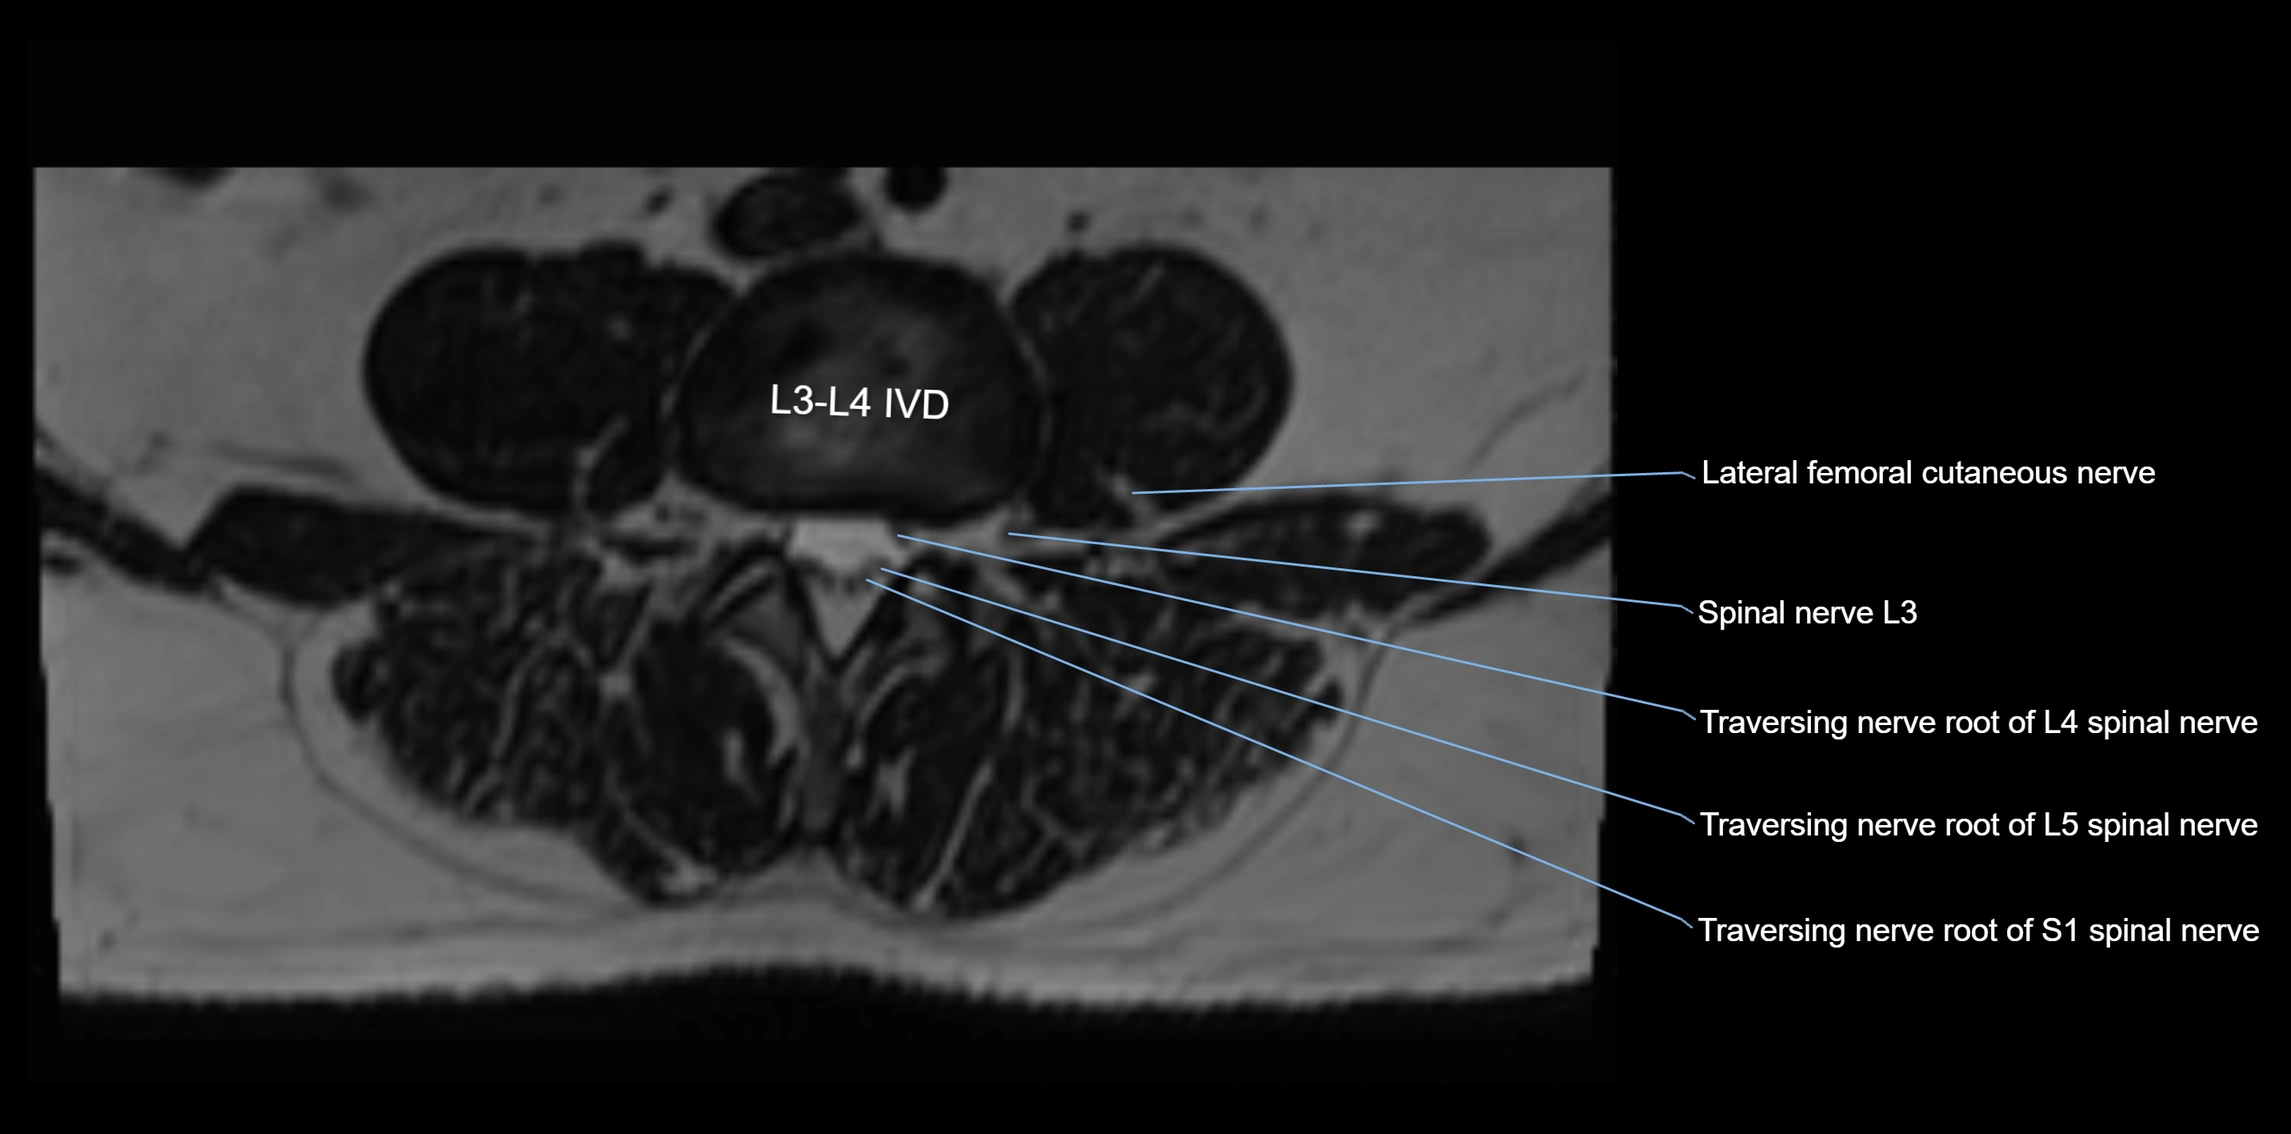

MRI Appearance

T1-weighted images:

• Nerve appears as a very thin low-to-intermediate signal intensity structure

• Surrounded by bright fat, aiding visualization

T2-weighted images:

• Nerve shows intermediate to mildly hyperintense signal compared to muscle

• Pathological involvement appears brighter

STIR (Short Tau Inversion Recovery):

• Normal nerve appears dark

• Inflamed or entrapped nerve appears bright hyperintense

T1 Fat-Sat Post-Contrast:

• Normal nerve enhances minimally

• Pathologic nerve (neuritis, entrapment, tumor infiltration) shows focal or diffuse enhancement

3D T2 SPACE / CISS:

• Nerve appears intermediate to mildly hyperintense compared to muscle

• Surrounded by bright fat or CSF, improving visualization

• Best sequence for mapping small pelvic nerves such as the anococcygeal